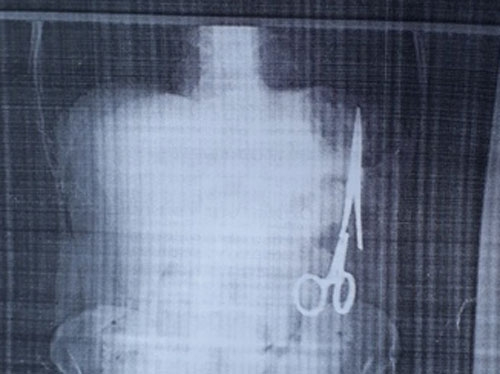

Nội dung bài báo phản ánh về trường hợp của ông Ma Văn Nhật, 54 tuổi, trú tại xã Bình Trung, huyện Chợ Đồn, tỉnh Bắc Kạn sau khi đi khám đã phát hiện trong ổ bụng có một chiếc kéo/panh dài 15 cm.

Tuy nhiên, thời gian gần đây ông thấy đau nhói ở bụng sau một lần việc quá sức, ông Nhật vào Bệnh viện Gang thép Thái Nguyên khám. Kết quả siêu âm ngày 25/12 cho thấy trong ổ bụng của ông có một chiếc kéo dài khoảng 15 cm, được cho là chiếc panh chuyên dùng để mổ của ngành y.

2 ngày sau ông đến siêu âm tại Bệnh viện đa khoa Bắc Kạn, kết quả tương tự. Và theo ông Nhật, trừ lần phẫu thuật cách đây 18 năm, ông chưa phải vào viện mổ lần nào nữa.